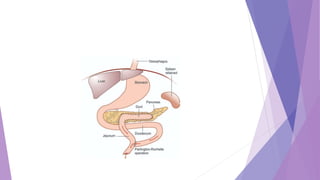

 Partington – Rochelle operation: Here longitudinal pancreaticojejunostomy is

done using almost entire laid open pancreatic duct. Spleen is retained in this

procedure. This is now commonly done procedure.

 Longitudinal dochotomy in obstructing calcific pancreatitis(Partington and

Rochelle)